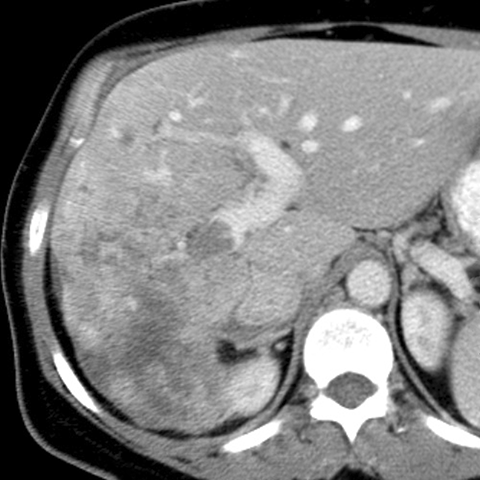

67 year-old male presents with weight loss, fatigue and jaundice. [1 of 2]